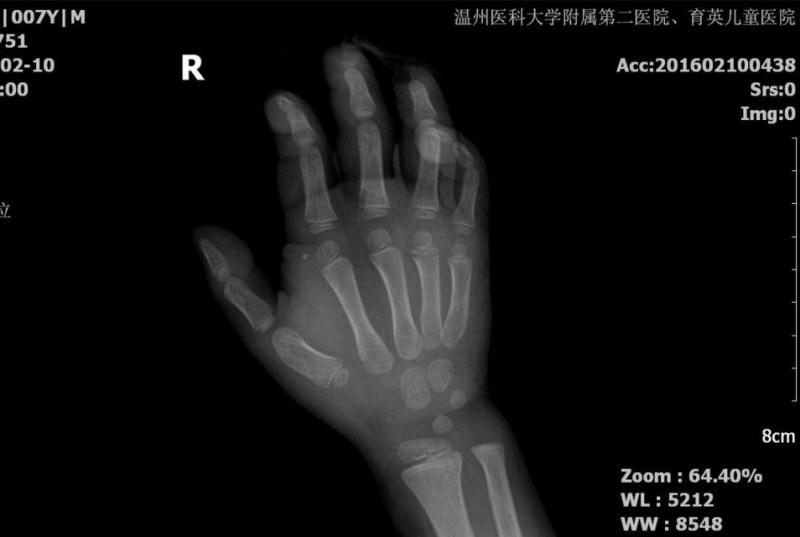

当天晚上,一位家长急匆匆地带着右手已是血肉模糊的孩子前来就诊,值班医生询问病史后得知,是因为孩子燃放鞭炮时竟因一时好奇,将鞭炮点燃之后并没有往远处投掷,而是将它直接捏在了手掌心。之后,鞭炮爆炸产生的巨大威力,直接将患儿的右手中指、环指末节指骨炸断,手掌炸出了一个面积约9平方厘米,深约2-3mm的“窟窿”,创面一直在不停地渗血,同时伴有多个大大小小不等的水泡。值班医师迅速给患儿安排了急诊手术。手术过程虽然比较顺利,但令人痛心的是,这个才7岁的孩子却从此再也不能像正常人一样灵活地使用右手手指了。